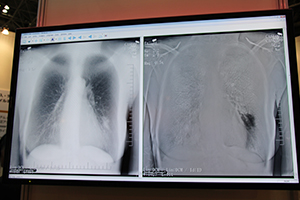

ブースの前面では,胸部X線読影診断ソリューション「ClearReadシリーズ」を大きく展示した。ClearReadは胸部X線画像の骨組織を透過するソフトウエアで,院内にサーバを設置・設定しておくことで,モダリティからサーバへの画像転送,画像処理,そして処理画像の院内画像サーバへの転送が自動で行われる。オプションで提供される経時差分ソリューション「Compare」は,今回と前回の画像の差分を取って変化のあった部分を強調でき,別の撮影装置やメーカーの画像にも対応する。また,医療用チューブ強調ソリューション「Confirm」は,ポータブル装置を使った病棟での検査などで威力を発揮する。

胸部X線読影診断ソリューション「ClearRead+ Compare」の臨床画像。左が骨組織の透過処理画像,右が差分し経時的な変化を強調した画像。